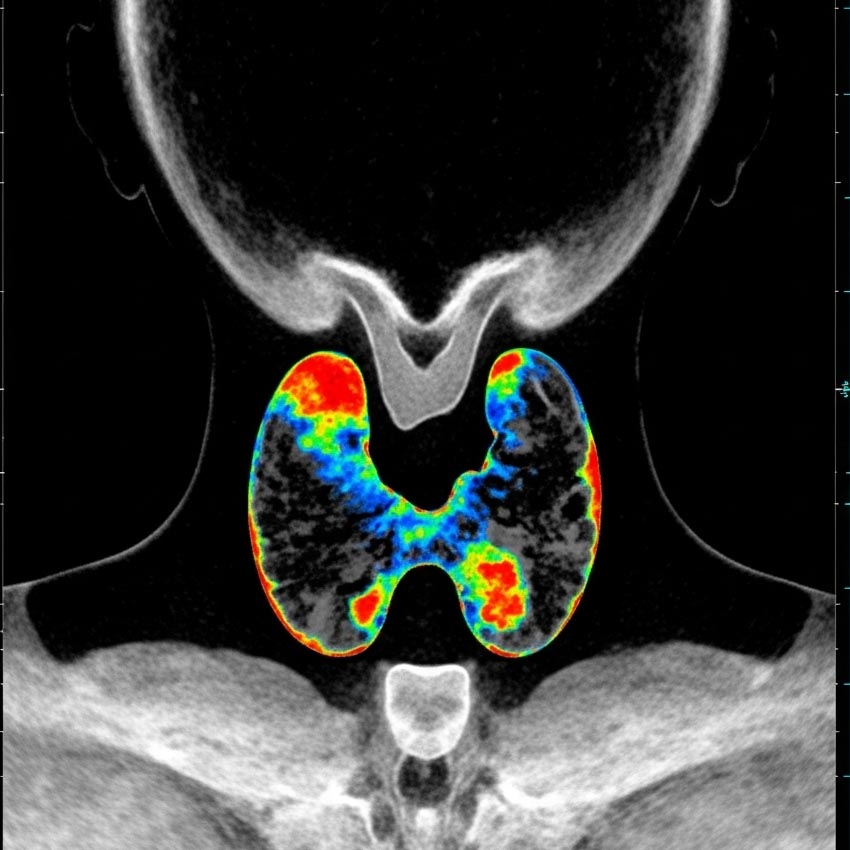

اسکن تیروئید و پاراتیروئید در تهران

مواردی که پزشک اسکن تیروئید را تجویز میکند:

1. بررسی علت بزرگی تیروئید (گواتر)

برای تشخیص اینکه گواتر منتشر است یا ندولار، و بررسی عملکرد نواحی مختلف غده.

2. بررسی ندولها یا تودههای تیروئید

برای تشخیص اینکه یک ندول "گرم" (فعال) است یا "سرد" (غیرفعال)؛ ندولهای سرد ممکن است نیاز به بررسی بیشتر داشته باشند.

3. ارزیابی پرکاری تیروئید (هیپرتیروئیدیسم)

برای شناسایی علت پرکاری؛ مثلاً بیماری گریوز یا آدنوم سمی.